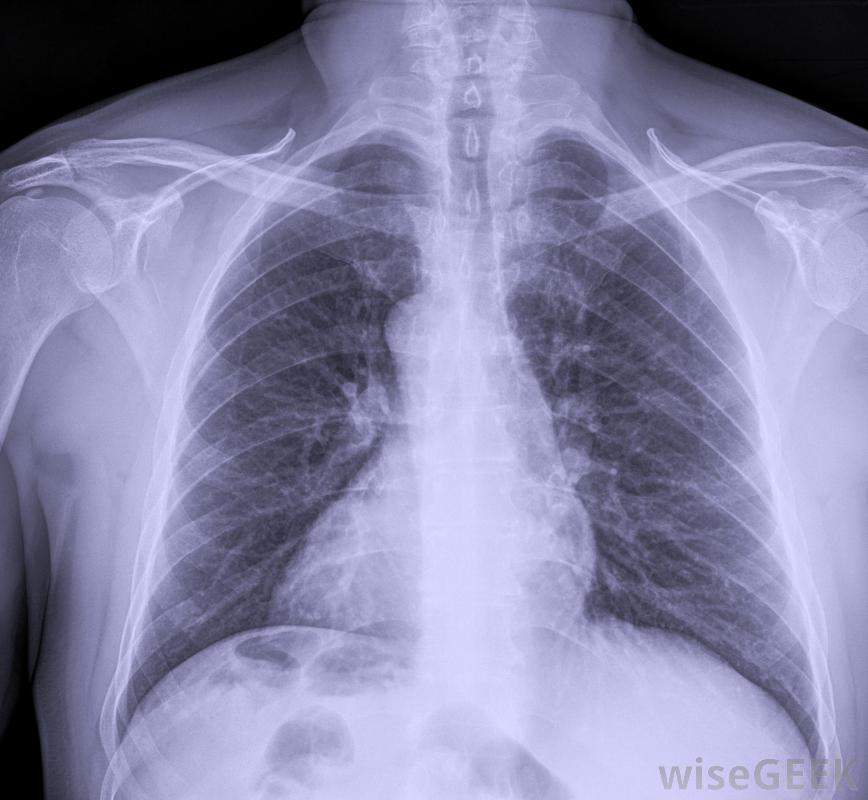

睪丸腫瘤是在睪丸或睪丸中發現的異常生長。腫瘤可以指任何一種異常生長,所以腫瘤可以是良性腫瘤或惡性腫瘤。惡性腫瘤是癌性的,而良性腫瘤不是。大多數睪丸腫瘤是癌性的,但幸運的是睪丸癌不是很嚴重常見,僅占所有男性癌癥的百分之一。睪丸腫瘤的前景通常是積極的,如果及時治療,很多都是可以治愈的。可以對睪丸腫瘤患者進行CT掃描,看看疾病是否已經擴散通常情況下,睪丸腫瘤是由生殖細胞或生殖細胞產生的。大多數腫瘤發生在繼續形成精子的細胞中,他們被稱為精原細胞瘤。非精原細胞瘤是由其他類型的生殖細胞形成的腫瘤。睪丸腫瘤最有可能發生在15至35歲的白人男性身上,但病因不明。最常見的癥狀是無痛性腫塊,盡管有些男性可能會感到睪丸疼痛或感到沉重。也可以進行胸部X光檢查,以尋找睪丸腫瘤擴散的跡象有時病人在睪丸腫瘤擴散后才會去看醫生,這會導致身體其他部位出現惡性腫瘤。腫瘤擴散的過程稱為轉移,新的腫瘤在身體不同部位的生長稱為轉移瘤。根據轉移灶的位置不同,癥狀可能包括咳嗽、呼吸困難、惡心、食欲不振、背痛或頸部腫塊。有些腫瘤分泌激素,會導致乳房腫脹,一種被稱為女性乳房發育癥的疾病。睪丸腫瘤可以通過放療和化療來治療睪丸腫瘤的診斷通常是通過超聲掃描來確定的。然后對骨盆和腹部進行胸部X光和CT掃描,以發現任何擴散的跡象。睪丸腫瘤的治療通常包括手術切除受影響的睪丸,以及附近的淋巴結。取決于腫瘤的類型和擴散的距離,手術后可進行放療或化療。可進行活檢以確定腫瘤是否為癌細胞精原細胞瘤早期治療預后良好對于I期癌癥,睪丸腫瘤在擴散到睪丸之前就接受了治療,大約95%的患者存活至少5年。非精原細胞瘤預后較差,約86%的男性在5年后仍然存活。治療成功后,患者通常定期隨訪檢查癌癥復發情況。睪丸腫瘤是睪丸或睪丸中發現的異常生長放射治療,如直線加速器,可用于幫助治療睪丸腫瘤。